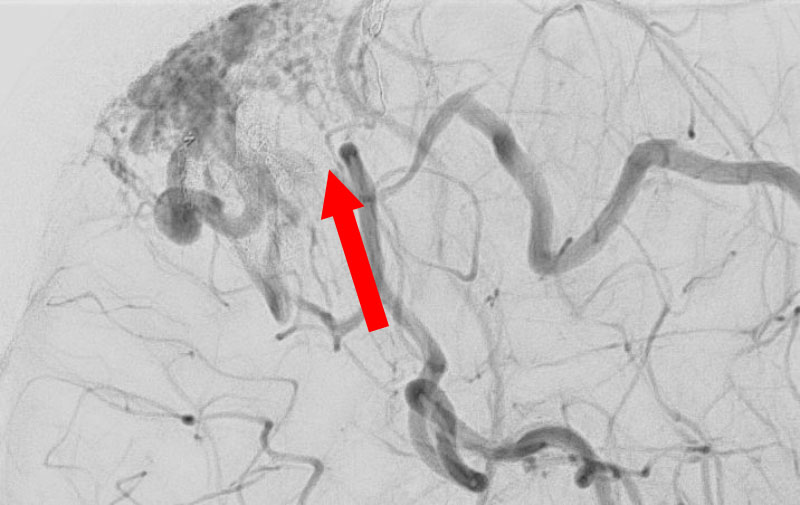

No.1596 手術後

'25年11月

左内頚動脈脳動脈瘤

60代

大阪府の病院